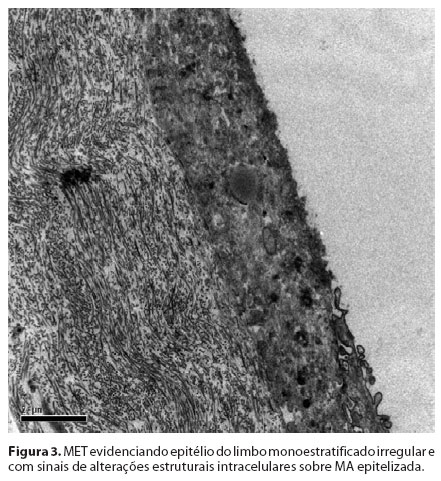

As células do Grupo 1 (MA desepitelizada) as células apresentaram-se bem-estratificadas e diferenciadas com 4 a 5 camadas. Foi observado que as células basais encontravam-se bem aderidas a MA com a formação de hemidesmossomos e a produção de material de membrana basal (Figura 3/Figura 4). Por outro lado, no Grupo 2 (MA intacta), o epitélio monoestratificado apresentava grandes espaços adjacentes entre as células. Estas células não estavam bem aderidas à membrana basal e apresentavam pouca evidência de material de membrana basal. Os espaços entre as células eram largos e com poucos desmossomos.